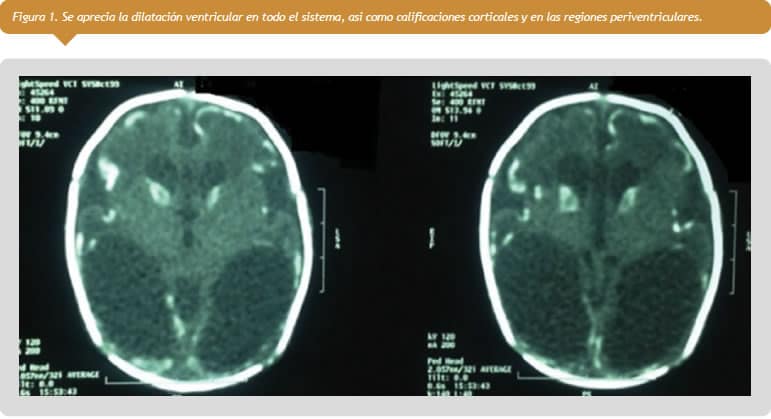

Debido a los antecedentes antes mencionados de toxoplasmosis durante su gestación, se decidió realizar una tomografía axial computarizada de cerebro a los tres días de nacida (Figura 1 ver a la derecha). Sin embargo, se desconoce la decisión del grupo tratante de la paciente en el otro centro de salud ya que la madre no tenía una copia de la historia clínica sino únicamente la copia de las imágenes de tomografía.

En los pacientes pediátricos predominan tres tipos de calcificaciones: congénitas, infecciosas y neoplásicas [13]. Dentro de las congénitas se encuentran enfermedades como el síndrome de Sturge-Weber, neurofibromatosis, síndrome de Cockayne y lipomas [12],[13]. Las calcificaciones por neoplasia se presentan principalmente en craneofaringioma, oligodendroglioma, neoplasias de células germinales, tumores neuroectodérmicos (DNET), meningioma, papiloma del plexo coroideo, astrocitoma pilocítico y metástasis, entre otros [12]. Dentro de las causas infecciosas se destacan enfermedades TORCH (toxoplasmosis, rubéola, infección por citomegalovirus, herpes simple y sida), infecciones granulomatosas y encefalitis virales [12],[13]. Vale la pena destacar que aunque son múltiples las causas de calcificaciones intracraneales, la mayoría de ellas tiene un patrón distintivo en la tomografía axial computarizada de cráneo. Para la toxoplasmosis congénita las calcificaciones son nodulares y se encuentran en las regiones periventriculares, ganglios basales y en la corteza cerebral asociadas, en la mayoría de los casos, con hidrocefalia [5],[11],[12].